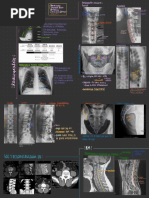

Arterias bronquiales patológicas en LII.

Son vasos malformados.

Es el mismo caso del a foto anterior pero

después de la embolización, ya no se ven

las arterias malformadas

Control del caso anterior

Arterias bronquiales derechas

patológicas

Después de la embolización ya no se

ven